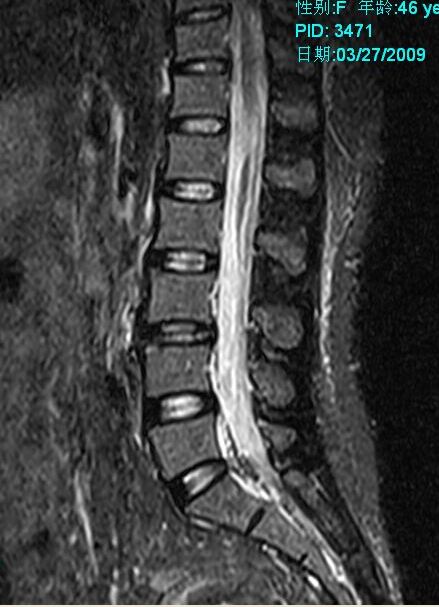

标题: MRI2099:此病人加做压脂像确诊为:终丝脂肪浸润。 [打印本页]

标题: MRI2099:此病人加做压脂像确诊为:终丝脂肪浸润。

此病人加做压脂像:腰1、2椎体平面椎管内条状高信号病灶信号明显降低。以下为压脂像图像: